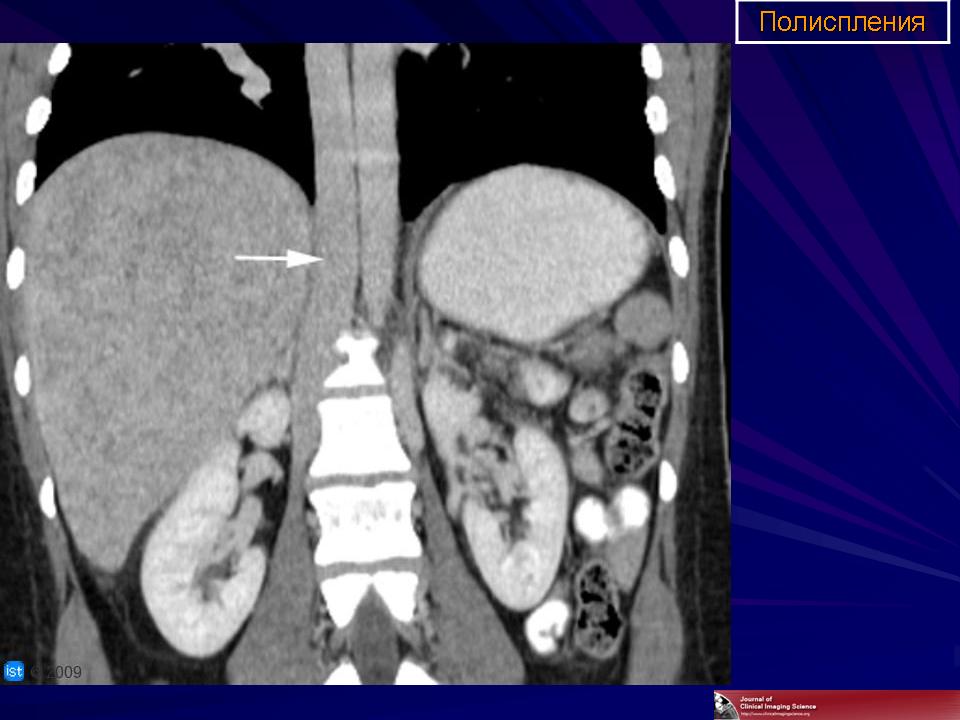

Полиспления

ID: 18841 Polysplenia syndrome Dr Ian Bickle - 24 Jul 2012 Features of polysplenia syndrome (aka left sidedness or left isomerism) ...

ID: 12761 Polysplenia syndrome , situs ambiguous, rectal mass Dr Amro Nazih Omar - 7 Jan 2011 Axial CECT demonstrates polysplenia, situs ambiguous, absent IVC an...